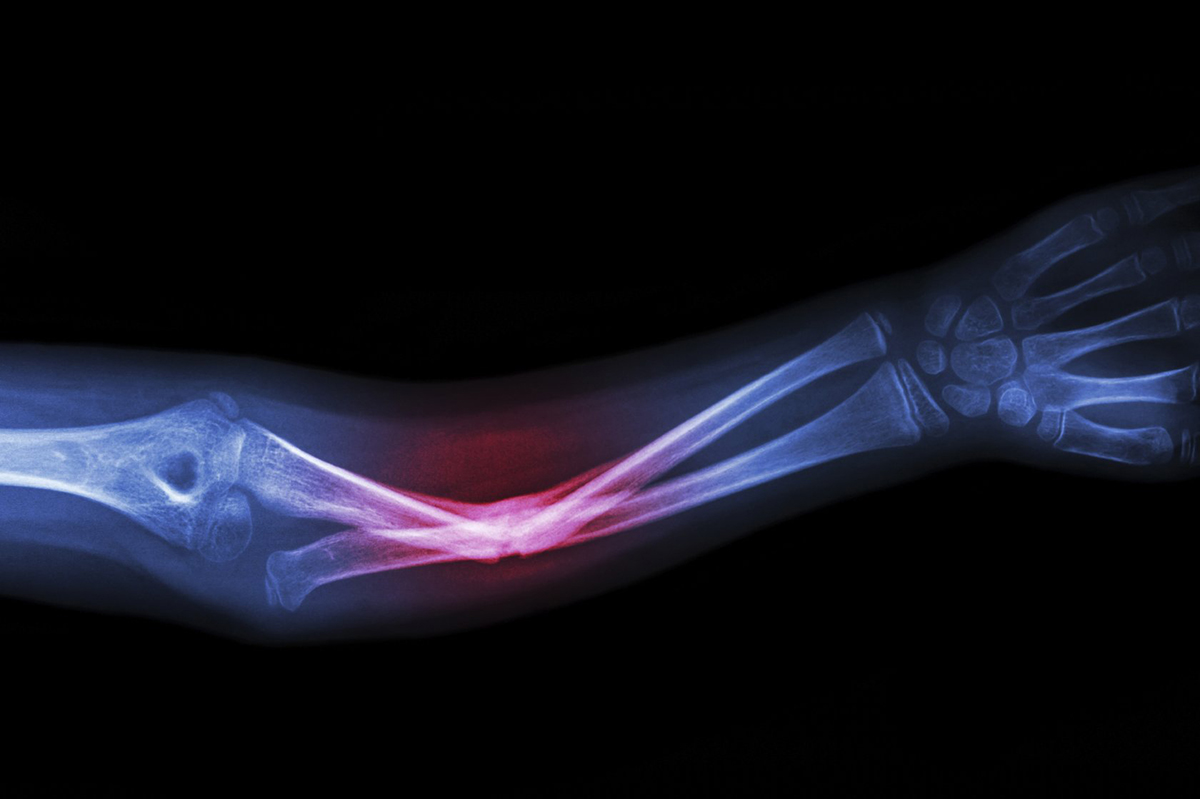

Тысячи пациентов в России и мире ежегодно сталкиваются с тяжелыми переломами костей скелета. Чтобы восстановить целостность кости и вернуть человеку подвижность, хирурги традиционно используют металлические конструкции – пластины, кольца, стержни и спицы. Они выполняют роль внешнего каркаса, который прочно удерживает костные отломки в правильном положении, пока идет долгий процесс сращения.

На снимках и компьютерных томограммах (КТ) металлические конструкции создают сильные помехи, которые в медицине называют артефактами. Это яркие размытые тени, которые «засвечивают» самую важную область – место перелома. При том, что за время лечения пациент проходит несколько контрольных рентгеновских исследований, хирург вынужден буквально заглядывать за этот «слепящий» экран, рискуя пропустить смещение костных фрагментов или проблемы со сращением.

Испытания проводили на цилиндрических образцах из углерод-углеродного композита диаметром 4 мм, которые подобны реальным стержням аппаратов наружной фиксации – такие конструкции накладывают на сломанную руку или ногу, чтобы зафиксировать кость в правильном положении. Ранее для этих целей рентгенопрозрачные композиционные материалы не применяли.

Таким образом, незначительное падение прочности во всех режимах испытаний подтверждает, что углерод-углеродный композит пригоден для использования в аппаратах внешней фиксации. Даже после экстремальных доз облучения материал сохраняет от 88 до 94% исходных показателей и этого запаса достаточно, чтобы выдерживать вес пациента без риска разрушения. При этом углепластик полностью прозрачен для рентгена: так что врач увидит зону перелома без помех и искажений.